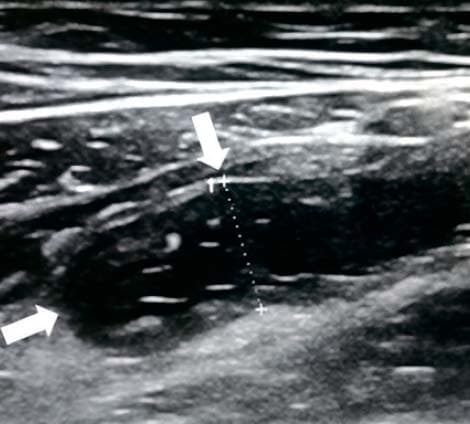

Обнаружение увеличенных лимфоузлов (более 5 мм в поперечнике) по ходу корня брыжейки тонкой кишки является вторичным признаком воспаления в илеоцекальной области при остром аппендиците (см. рис. 14). Этот признак неспецифичен для острого аппендицита, поскольку лимфаденопатия в брюшной полости может быть как при аппендиците, так и без него, являясь частой реакцией на воспалительные заболевания толстого и тонкого кишечника, а также может отмечаться при первичном мезадените. Увеличенные лимфоузлы имеют вид гипоэхогенных овальных структур, несжимаемых при компрессии.

Рисунок 14. Увеличенный лимфоузел.